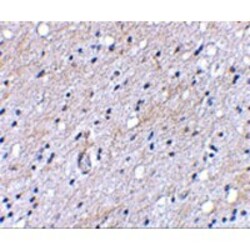

- Immunohistochemical staining of human brain tissue using BAP3 antibody at 5 µg/mL.